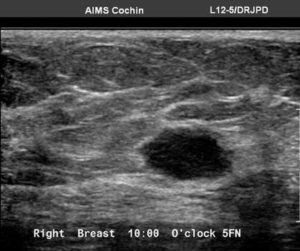

Ultrasound showed two hypoechoic solid masses in upper outer quadrant. The larger one has moderate vascularity and angular margins. Normal axillary lymph nodes.

Ultrasound guided 14 G core biopsy from larger mass showed solid papillary carcinoma with a suggestion to exclude neuroendocrine tumour origin.

Ultrasound guided wire localisation along with lumpectomy and SLNB was performed. Final HPE showed the larger mass to be Primary Breast Non- Hodgkin’s lymphoma, diffuse large B cell type. Another nodule seen is a hyalinised fibroadenoma. Axillary lymph nodes were not involved.

US: Variable presentation, hypoechoic, irregular mass with indistinct margins, may have no internal vascularity on colour Doppler evaluation in up to 55 % of cases. Posterior acoustic shadowing is not a feature and this may be due to lack of desmoplastic reaction.